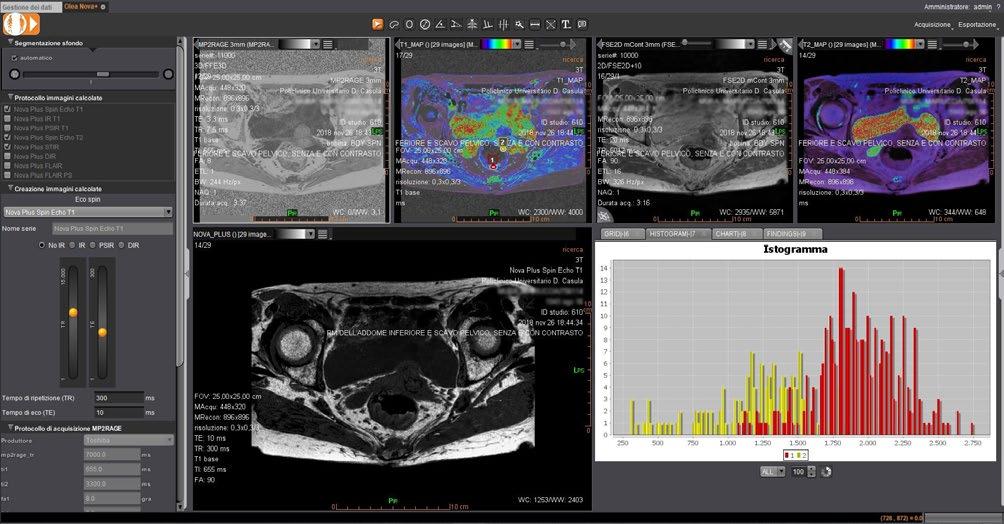

Figure 2, Axial MRIs of the brain. Left: T1-weighted image (short TE and TR). Right: T2-weighted image (long TE and TR). Figure 3, Olea Nova + software. Top row: MP2RAGE images from which the T1-map is calculated and FSE mEcho images used to calculate the T2-map. Bottom row: Two synthetic images with different imaging parameters.

Canon Medical MR systems require two sequences to be able to calculate T1 and T2 relaxation times. To measure the T2-relaxation time, we use a 2D FSE mEcho (2D Fast Spin Echo Multi-Echo) sequence. This sequence acquires the signal multiple times after an excitation pulse (illustrated by dots in the T2-relaxation graph in Figure 1). The longer the time between the excitation and the signal acquisition (TE), the smaller the transverse magnetization becomes. This is an exponential process and the Olea software fits the data points to obtain the T2-relaxation time (Figure 3 – top right).

For the computation of the T1 relaxation time, we use a MP2RAGE sequence (Magnetization Prepared 2 RApid Gradient Echo). This sequence starts with inverting the longitudinal magnetization of all tissues and samples the regrowth of the magnetization at two different time points after this inversion. In the Olea software, the signal intensity at these two time points is fitted and the T1 relaxation time is determined at each voxel (Figure 3 – top middle). Before the fitting process of both the T1 and T2 relaxation times, motion correction is applied.

Now that the T1 and T2 relaxation time is known at every position in the image, the software can synthesize new contrasts using signal equations that describe the signal intensity based on the T1, T2, TE, TR and TIs (inversion times). To create a T1-weighted

image, a short TE and TR can be selected. The software then calculates the contrast obtained with these settings, presenting the result immediately. This new synthetic image can be saved and exported. To change the contrast again, the parameters can be altered (Figure 4) and a new image is created, without the patient needing to be present.